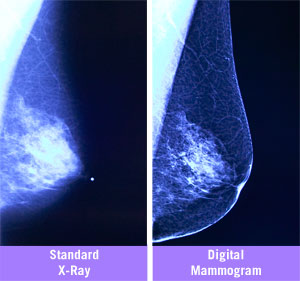

DIGITAL MAMMOGRAPHY

Mammography is the process of using low dose amplitude X-rays to examine the breast and is used as a screening and diagnostic tool. The goal of mammography is early detection of breast cancer, typically through detection of characteristic masses and micro calcification.